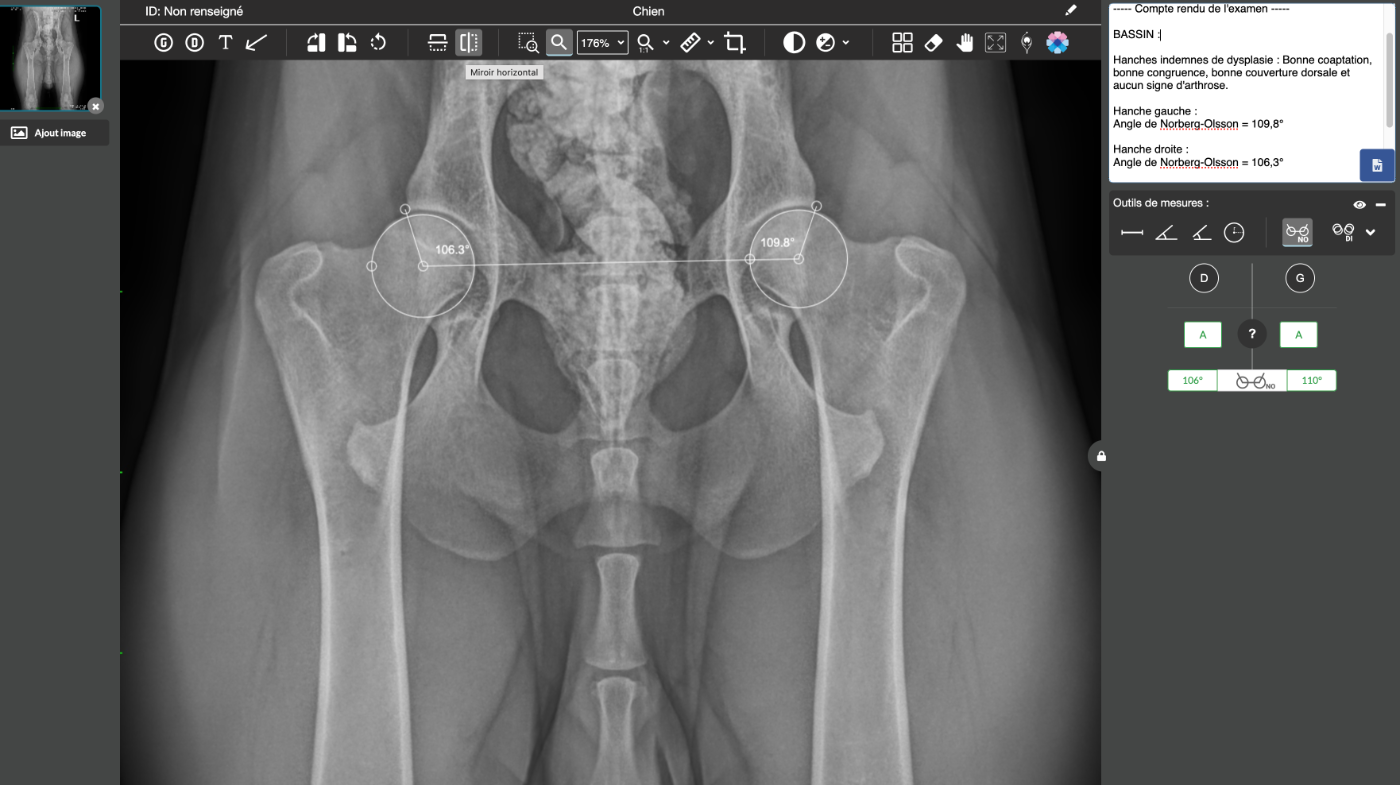

Dentition & Testicules : DCC - Chien complet Dysplasie Hanches : Trop jeune - Prévision 2026, à l'âge de 15 mois Dysplasie Hanches : Trop jeune - Prévision 2026 à l'âge de 15 mois Poils Longs : Non Porteur Sensibilité Médicamenteuse : Sain (N/N) |